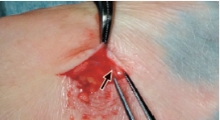

- Ⓐ足背(足の甲)に切開を入れて、リンパ管を穿刺して本剤を緩徐に注入する。